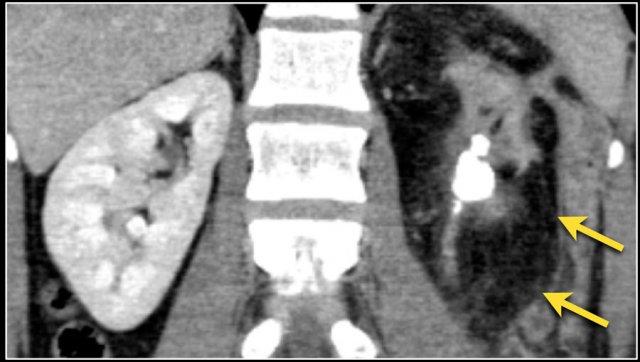

Hình ảnh cho thấy tổn thương thận hai bên và tổn thương xương ở bệnh nhân u lympho tế bào B.

Đây là một bệnh nhân khác với u lympho khu trú tại trung thất, tụy (mũi tên) và cả hai thận.

PET-CT cho thấy tổn thương thận lan tỏa và các hạch bạch huyết cạnh động mạch chủ dương tính (mũi tên).

Có một tổn thương di căn ở thận trái và nhiều tổn thương di căn hạch bạch huyết (mũi tên).

Nếu đây là biểu hiện duy nhất, sẽ rất khó để phân biệt với ung thư biểu mô tế bào thận có di căn hạch bạch huyết.